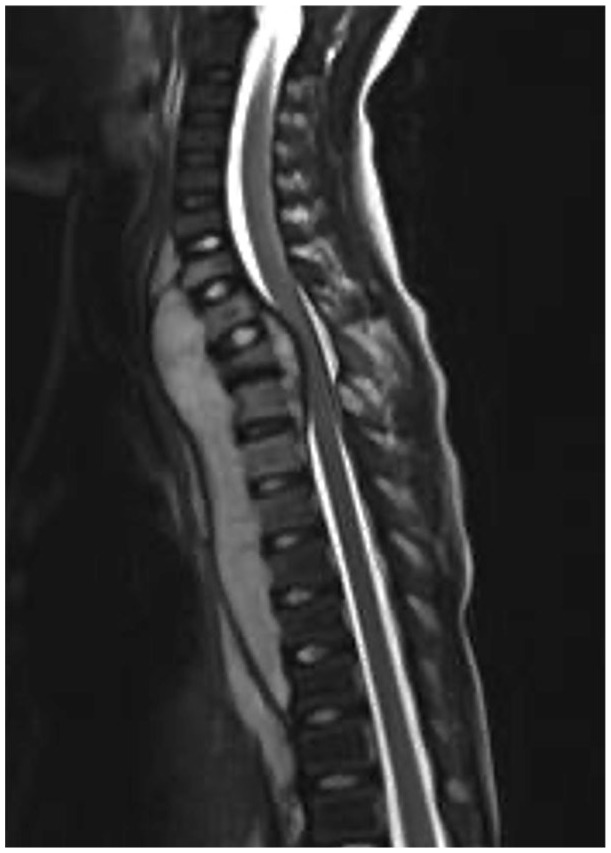

背部疼痛是儿童和青少年中比较常见的主诉。小儿患者的背部疼痛往往是具有挑战性的,有许多众所周知的有机诊断不应该错过。在年幼的儿童中,经常可以发现背部疼痛的器质性原因。然而,年龄较大的儿童和青少年的背痛通常是“非特异性的”。儿童背痛的鉴别诊断包括肿瘤、发育和炎症。基本步骤应包括深入的记忆、系统的体格检查和标准的脊柱x线片(前后位和侧位)。然而,先进的诊断成像和实验室研究应包括当指,以避免遗漏或延误严重的诊断。如果需要其他类型的影像学检查(磁共振成像、计算机断层扫描、骨扫描或单光子发射计算机断层扫描),则应以诊断怀疑为指导。

Back pain is a relatively common complaint in children and adolescents. The pediatric patient presenting with back pain can often be challenging, and there are many well-known organic diagnoses that should not be missed. In younger children, an organic cause of back pain can often be found. However, back pain in older children and adolescents is often "non-specific." The differential diagnosis of back pain in children includes neoplasms, developmental, and inflammatory conditions. Basic steps should include an in-depth anamnesis, a systematic physical examination, and standard spine radiographs (anteroposterior and lateral). Nevertheless, advanced diagnostic imaging and laboratory studies should be included when indicated to avoid missing or delaying a serious diagnosis. If other types of imaging tests are necessary (magnetic resonance imaging, computed tomography, bone scan, or single photon emission computed tomography), they should be guided by diagnostic suspicion.